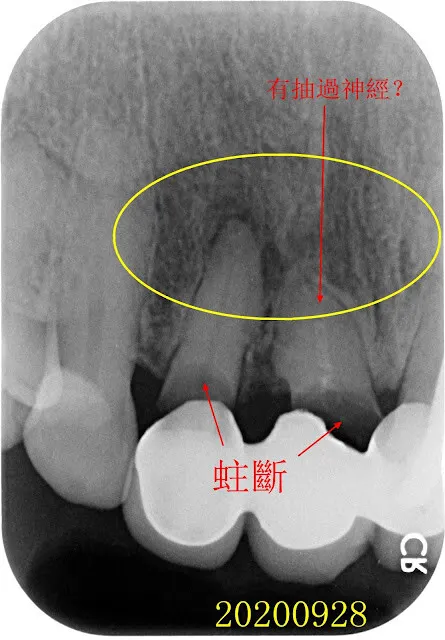

紅圈是非拔不可的牙齒,蛀到剩殘根(R.R.),這部分比較沒有異議。 牙齒殘根為何一定要拔?不拔會怎樣嗎? 我想很多人會有疑問,所以我問了M$的Copilot,AI的回答如下(令人汗顏,整理的真好,所以我直接複製貼上引用).... 本文的重點我想放在模擬治療計畫,順便說說智齒矯正取代。